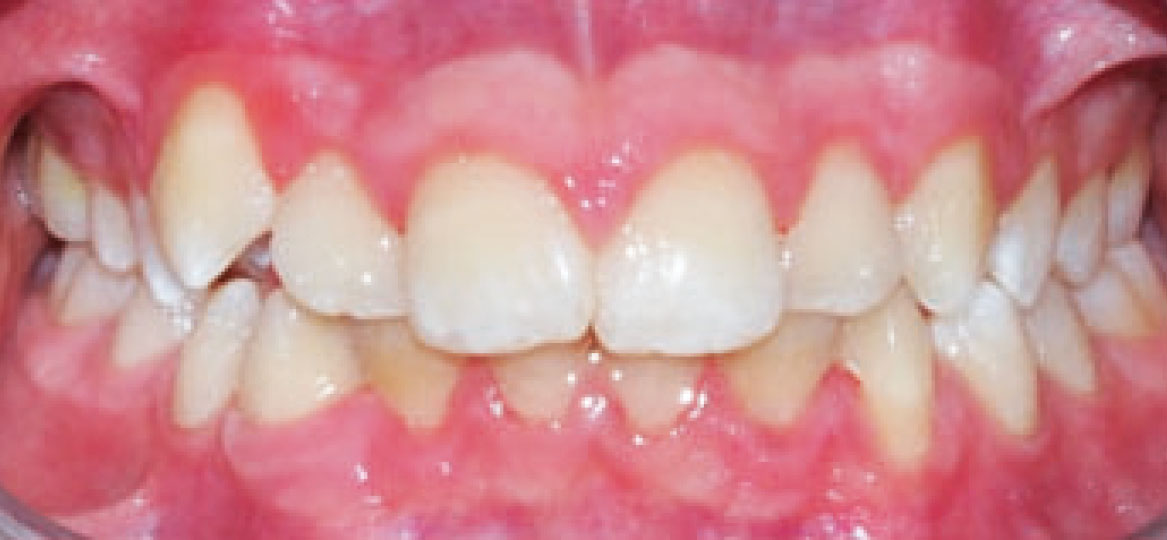

Dall’esame obiettivo intra orale si osservava una seconda classe canina destra e sinistra, una seconda classe molare destra e sinistra, e un diametro inter-canino e inter-molare ridotto sia in riferimento al mascellare superiore sia al mascellare inferiore (fig. 3A-3E).

Clinical examination revealed high caries risk, poor oral hygiene, and constricted upper and lower arches.